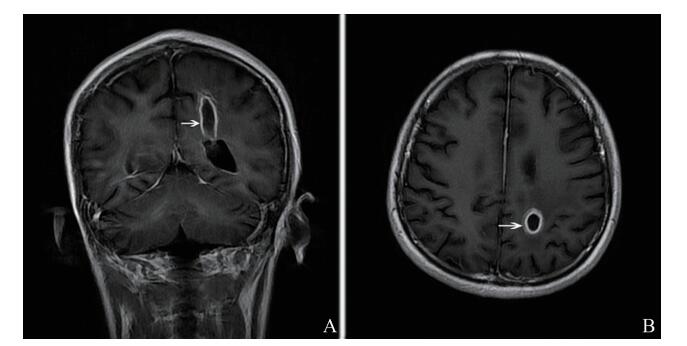

例2 患者女,52岁。因“头痛、复视2个月,四肢抽搐11 d”于2017年9月19日入中山大学附属第三医院。入院前2个月患者出现头痛,为全头胀痛,伴有复视,偶有肢体乏力,无言语不清。入院前11 d患者突发四肢抽搐,口吐白沫,约2 min后自行缓解,其后多次发作。既往有SLE、狼疮性肾病病史,入院时口服甲泼尼龙16 mg/次、1次/日,硫酸羟氯喹0.2 g/次、2次/日。入院时体格检查:体温36.4 ℃,神志清晰、对答切题,双侧瞳孔等圆等大,直径3 mm,对光反射灵敏,眼球各方位活动正常,双侧眼底未见视乳头水肿。四肢肌张力正常,双上肢肌力5级,左下肢肌力3级,右下肢肌力4级,左侧巴宾斯基征阳性,右侧巴宾斯基征阴性。颈软,颌胸距2 cm,克匿征阴性,布鲁津斯基征阴性。心、肺、腹未见异常。实验室及辅助检查:血白细胞13.02×109/L,中性粒细胞0.88。腰椎穿刺示脑脊液压力200 mm H2O,白细胞2×106/L,糖3.35 mmol/L,氯94.2 mmol/L,蛋白6.19 g/L。头颅MRI示右侧额顶枕叶、左侧大脑脚脑桥及小脑半球、脑膜多发病灶(图 2A、B)。脑脊液mNGS示鼻疽诺卡菌、序列数1 043、置信度高。脑脊液涂片未发现病原体,脑脊液培养结果示鼻疽诺卡菌。诊断为诺卡菌脑膜脑炎,予磺胺甲

图 2 CNS诺卡菌感染例2患者头颅MRI A、B:治疗前头颅MRI图像,右侧枕叶T2加权像上见类圆形长T2信号影,边缘见等信号壁,病灶周边环形低信号(A箭头所指处),额顶枕叶、小脑脚多发强化病灶(B箭头所指处); C、D:治疗后头颅MRI图像,右侧枕叶T2加权像上病灶呈斑片状长T2信号,较前吸收、缩小,邻近周围脑实质内见片状稍长T1稍长T2信号水肿区,范围较前缩小(C箭头所指处),额顶枕叶多发强化病灶,强化灶较前减少、缩小(D箭头所指处) |

诺卡菌感染与其它脑脓肿一样,MRI下注射钆后显示出病变的坏死中心和多叶厚壁环状强化,T2加权像上的周边环形低信号被认为是由坏死组织碎片和巨噬细胞对夹膜的吞噬作用所形成,而厚荚膜的产生是因为诺卡菌生长缓慢及宿主抵抗细菌的过程中所发生的外周变化[9-10]。诺卡菌感染若能早期治疗,病灶可明显减少、缩小。